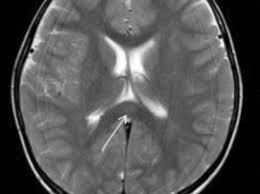

Welche dieser Folgen dauerhaft bleiben könnten, wird gerade untersucht. Ungefähr bei einem Drittel der Corona-Patienten auf den Intensivstationen sind diffuse Hirnschädigungen aufgetreten, die zu Gedächtnisproblemen, Aufmerksamkeits- und Konzentrationsschwierigkeiten führen könnten, sagt Peter Berlit, Generalsekretär der Deutschen Gesellschaft für Neurologie: Solche Patienten können verwirrt sein, haben Fehlwahrnehmungen und Halluzinationen.

Studie: Hirnschäden treten schon bei leichten Covid-19-Symptomen auf

Immer mehr Studien berichten von Corona-Patienten, die nach einer Covid-19-Erkrankung Hirnschäden davontragen. Forscher berichten von weitreichenden Komplikationen, darunter Schlaganfälle, Hirnentzündungen und Psychosen. Neurologische Schäden sind demnach auch bei einem milden Krankheitsverlauf und bei jüngeren Patienten möglich. Britische Forscher haben bei der Untersuchung von Covid-19-Patienten festgestellt, dass selbst diejenigen mit leichten Symptomen unter schwerwiegenden Hirnschäden leiden können. Demnach kommt es häufiger als bisher vermutet zu Folgeschäden, darunter Nervenschäden, Fieberwahn und Schlaganfälle, wie Forscher vom University College London berichten. Das könne auch zum Tode führen. Auch bei bereits als genesen Geltenden wurden Schäden festgestellt, heißt es in der in der medizinischen Fachzeitschrift Brain

veröffentlichten Studie.

Hirnentzündung und Nervenschäden häufiger als vermutet

Wir konnten mehr Patienten mit neurologischen Schäden wie Entzündungen im Gehirn identifizieren als gedacht

, sagte Michael Zandi vom Forscherteam. An der Studie nahmen 43 Menschen teil, die an Covid-19 erkrankt sind oder bei denen eine Infektion vermutet wurde. Das Ergebnis: Zwölf der Probanden hatten eine Hirnentzündung, zehn eine vorübergehende Hirnfunktionsstörung und acht Nervenschäden. Nicht jedem Befund ging eine schwere Covid-19-Erkrankung voraus - Hirnschäden sind also auch nach einem eher milden Verlauf der Erkrankung möglich. Die Art und Weise, wie Covid-19 das Gehirn attackiert, haben wir bei anderen Viren noch nie zuvor gesehen

, sagte Zandi.